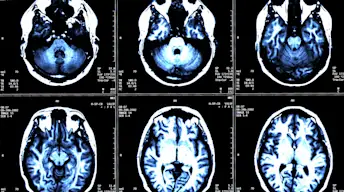

MS病变如何表格?

对于我们的MINI MED学校视频系列,我们打破了MS如何损害身体神经并导致其最常见的症状。